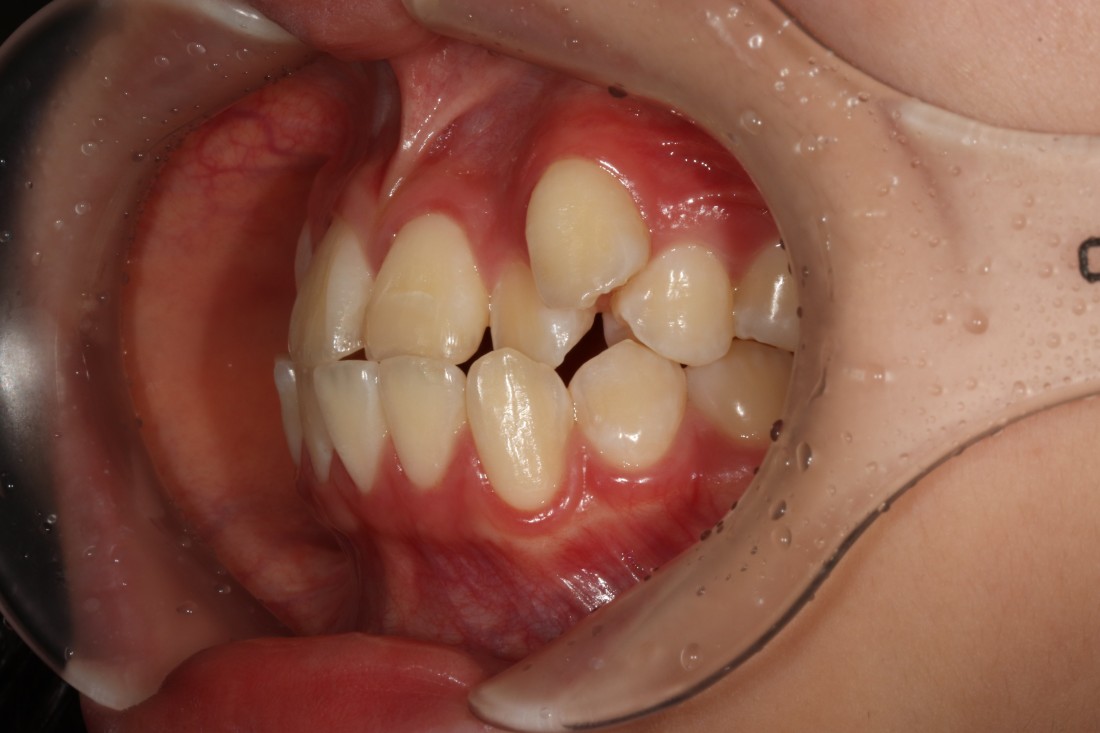

수완동 교정치과를 선택할 때는

교정전문의가 경험이 풍부한지,

교정전문의가 상담부터 진료 후 관리까지

책임지고 진료하는 곳인지

꼼꼼하게 따져보는 것이 중요합니다.

서울우리아이치과는

20년 이상 교정진료만을 담당해오신

교정전문의 대표원장님께서

교정진료의 시작부터 끝까지

1:1 책임진료를 통하여

성공적인 치아교정을 완성하고 있습니다.